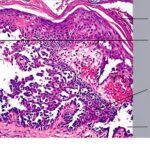

Histopathology. Although, as in Darier’s disease, early lesions may show small suprabasal separations, so-called lacunae, fully developed lesions show large separations, that is, vesicles and even bullae, in a predominantly suprabasal position . Villi, which are elongated papillae lined by a single layer of basal cells, protrude upward into the bulla, and in some cases, |

narrow strands of epidermal cells proliferate downward into the dermis. Many cells of the detached stratum malpighii show loss of their intercellular bridges; thus, acantholysis affects large portions of the epidermis. |

Individual cells and groups of cells usually are seen in large numbers in the bulla cavity. Despite the extensive loss of intercellular bridges, the cells of the detached epidermis in many places show only slight separation from one another, because a few intact intercellular bridges still hold them loosely together. This quite typical feature gives the detached epidermis the appearance of a dilapidated brick wall. |

Differentiation of familial benign pemphigus from Darier’s disease as a rule is not very difficult, because in Darier’s disease, the suprabasal separations usually are smaller, thus appearing as lacunae rather than as bullae; acantholysis is less pronounced, being limited to the lower epidermis, especially the suprabasal region; and dyskeratosis consisting of the formation of corps ronds and grains is much more evident. |

Differential Diagnosis. Histologically, familial benign pemphigus shares certain features with both Darier’s disease and pemphigus vulgaris. In all three diseases, one finds predominantly suprabasal separation of the epidermis caused by acantholysis and resulting in lacunae or bullae and villi formation. |